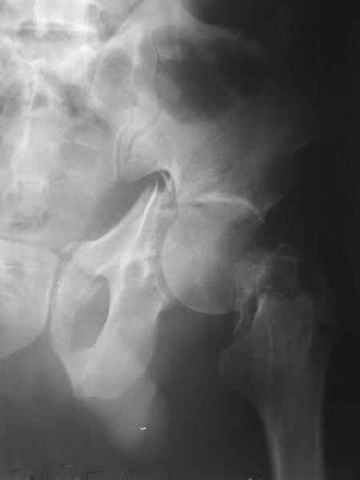

Сегодня из области к нам переведен мужчина 45 лет, 18 суток назад попал в автоаварию. Имеется перелом лонных и седалишных костей, двухколонный перелом вертлужной впадины, перелом шейки бедра и большого вертела. Еще и перелом проксимального отдела большеберцовой кости на этой же стороне, без больших смещений и импрессии.

Пока обсуждаем два основных варианта - 1)открытая репозиция вертлужной впадины, используя то, что вертел сломан. Попутно остеосинтез шейки винтами, а после и вертела. 2)А исходя из того, что в таком смещении головка бедра уже более двух недель и аваскулярный некроз ожидаем, возможно, первичное эндопротезирование было бы более оправдано. Но и оно проблематично из-за перелома впадины, при котором и крыло сломано.

A male 45 y.o. referred to our unit today. 18 days ago in a car accident sustained a fracture of pelvis, both column acetabular fracture, femoral neck and trochanteric fracture. There is also ipsilateral fracture of the proximal tibia but relatively not severe.

Two options are now discussing - 1)open reduction of the acetabulum through the broken trochanter, with ORIF of the neck at the same time. 2)Since the head is detached for more than 2 weeks and avascular necrosis is very likely, probably primary total hip replacement would be more reasonble. But it is also problematic in two column acetabular fracture and broken proximal femur.